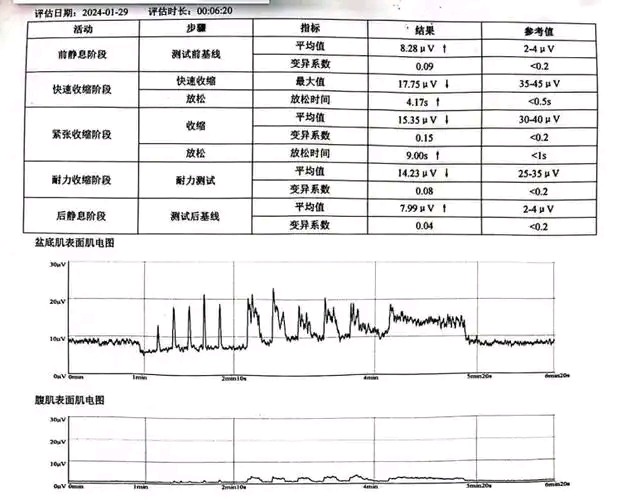

方法:通过表面电极记录盆底肌肉的电活动,评估其功能状态。

作用:评估盆底肌肉功能障碍,排除盆底失调综合征。